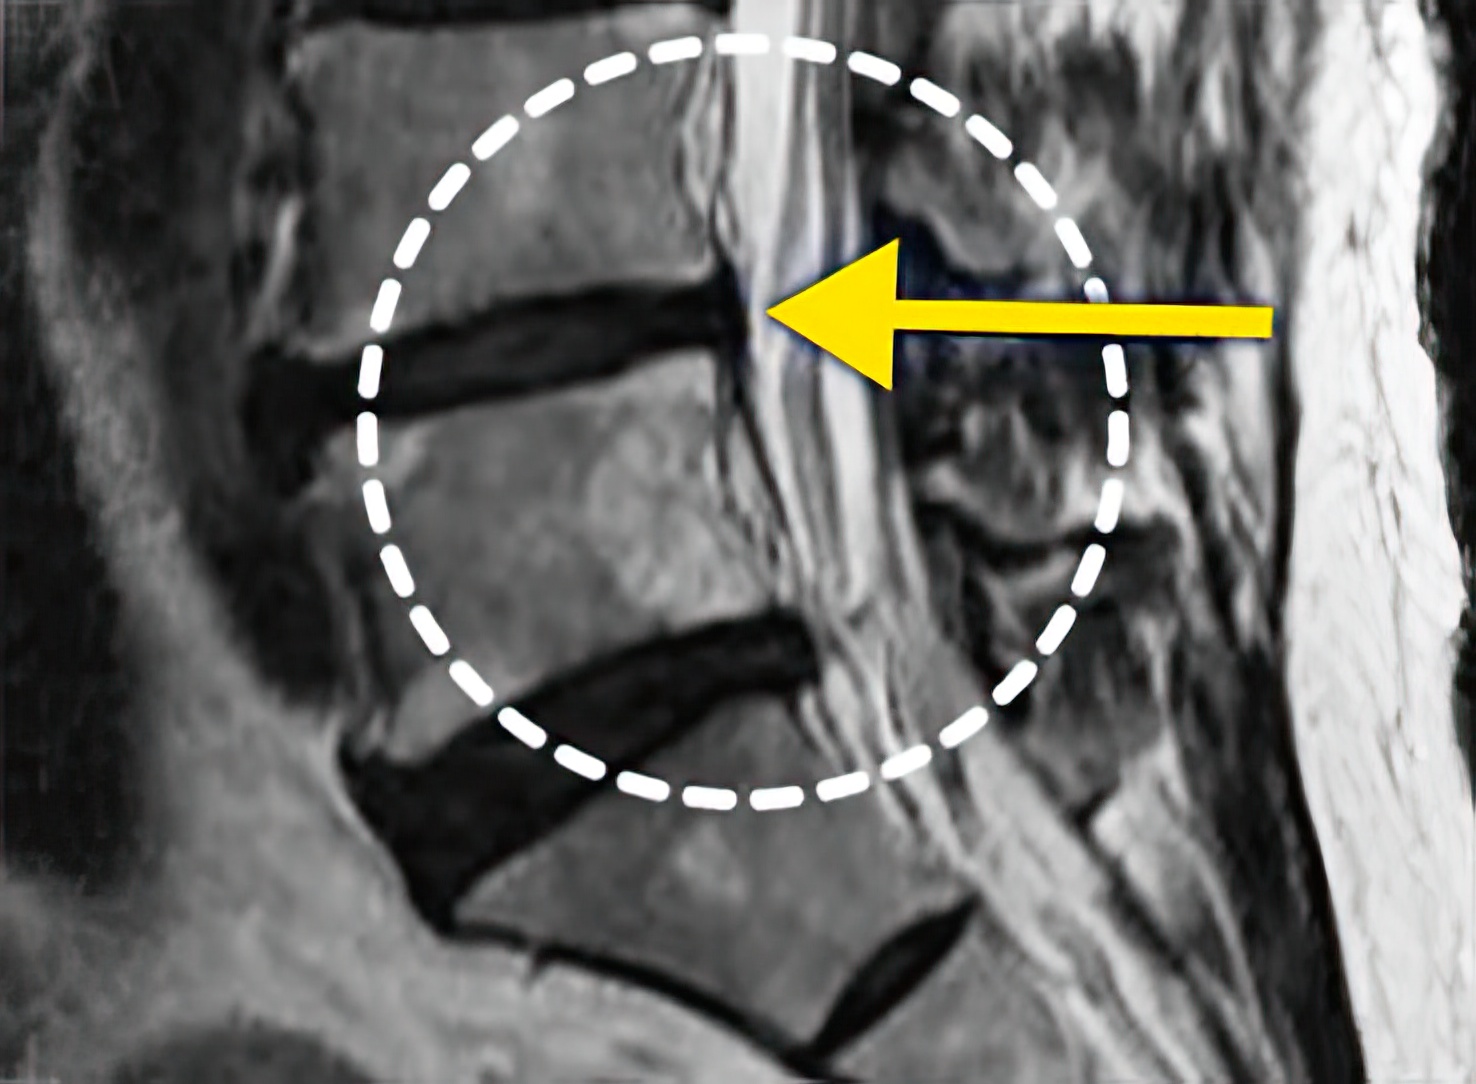

자생 비수술 한방통합치료 후

터진디스크가 흡수된 모습

Before

터진디스크 한방통합치료 전

비수술 치료만으로

터진 디스크 흡수

튀어나온 디스크 대비,

터진 디스크 치료 효과 우수

디스크 흘러내린 정도가

심할수록 흡수 가능성 증가